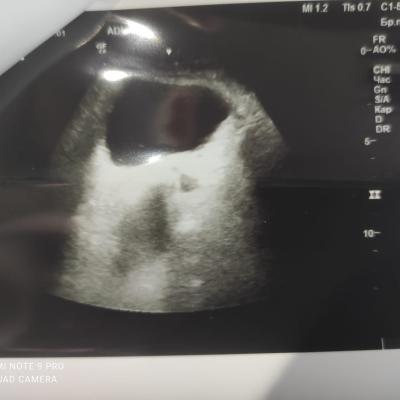

Здравствуйте! При наличии коралловидного камня правой почки(заключение УЗИ), можно предположить причиной боли нарушение уродинамики верхних мочевых путей), что, однако, не подтверждается результатами УЗИ почек( ЧЛС не расширена). Другая, наиболее вероятная возможная причина "боли в боку" - может быть патология опорнодвигательного аппарата. Необходимо проконсультироваться с неврологом и урологом очно, и согласовать возможность применения противовоспалительных, обезболивающих и спазмолитических препаратов - как первый шаг. В дальнейшем необходимо планировать возможное дальнейшее обследование и лечение. Удачи!